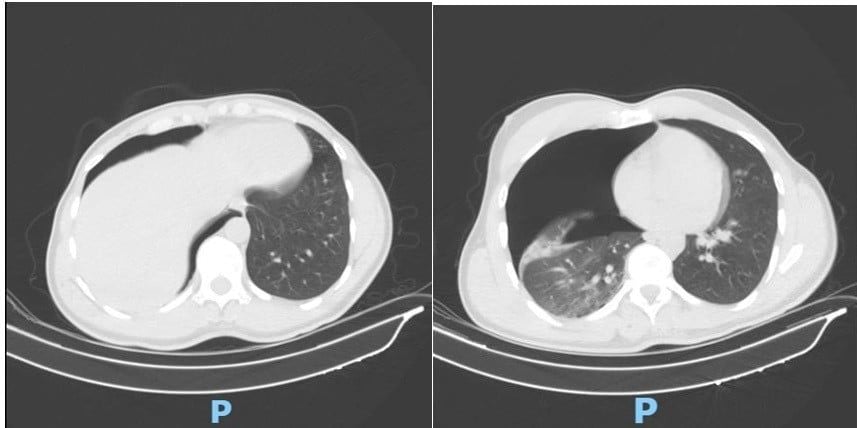

Phim CT scan lồng ngực sáng ngày nhập viện ghi nhận tràn khí màng phổi phải lượng nhiều

Ngay khi tiếp nhận, các bác sĩ đã khẩn trương thực hiện CT scan lồng ngực, mạch máu khẩn cấp. Kết quả cho thấy người bệnh bị tràn khí màng phổi phải lượng nhiều gây chèn ép phổi, gãy cung bên xương sườn 2, 3, 4 phải và gãy phức tạp 1/3 giữa xương đòn phải, di lệch nhiều kèm mảnh rời.